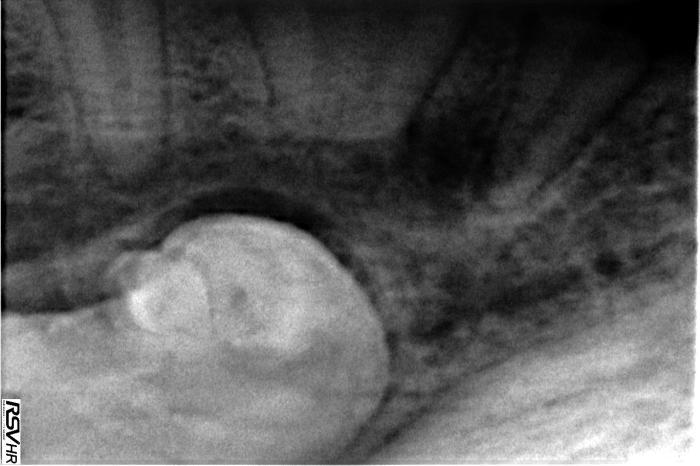

El estudio tomográfico permitió confirmar el diagnóstico de las alteraciones detectadas (Figuras 8 y 9).

Además, permitió comprobar la relación del diente 404 con los dientes 405 y 406, hallándose este ventral a ellos y al canal mandibular, estando ventral y medial a él. Se observó también que la silueta en la cara medial y ventral de la mandíbula estaba algo engrosada por la presencia del diente.

El presente caso destaca la relevancia de la exploración completa de la cavidad oral complementada con diagnóstico por imagen avanzada para planificar procedimientos de cirugía oral en pacientes con alteraciones dentarias complejas. La inclusión del diente 404 requiere una planificación minuciosa para evitar daños a estructuras anatómicas como el nervio alveolar inferior2. En este caso, el uso del TC fue muy útil para valorar la posición y relación con otras estructuras, principalmente los dientes y el canal mandibular.